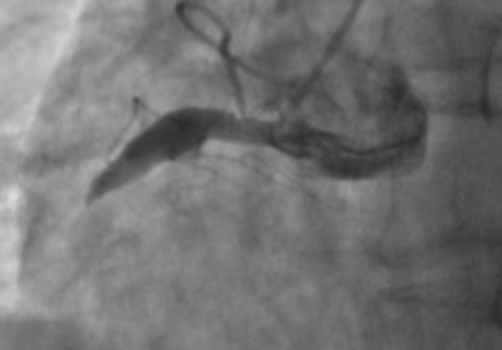

2023年09月14日下午4时35分,69岁的张大爷打牌中突然胸部闷痛,出大汗,就像是全身被浇了一盆凉水一样,非常难受。他电话联系家属乘车送我院胸痛中心。16:58到达医院大门,17:03查心电图示:窦性心律,Ⅱ、Ⅲ、AVF、V3R、V4R、V5R、V1-V4导联ST段抬高,T波高尖置。考虑急性ST段抬高型右室心肌梗死。立即给予心梗急救药物嚼服,吸氧、心电监护、建立静脉通道等紧急抢救措施。张大爷突然意识丧失,呼之不应,心电监护示室颤波形,先后进行2次紧急除颤。安得英医师团队迅速确定手术方案,建议马上进行“经皮右侧桡动脉穿刺下冠状动脉造影术+冠脉介入治疗”。随之迅速转运病人至介入导管室,冠状动脉造影提示严重冠脉闭塞病变,右冠第1段100%闭塞病变(图1),伴高负荷血栓影,高生云医师团队随即右冠内血栓抽吸术、溶栓术,打通闭塞血管(图2)。及时开通冠脉血流,为濒死的心肌重新供血(图3、图4)。从患者入门到开通血管仅用了47分钟。

图1 右冠近端急性闭塞